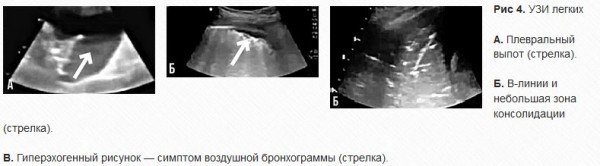

Мужчина, 74 года, без серьезных заболеваний в анамнезе, поступил 20 января на четвертый день заболевания с лихорадкой, кашлем и одышкой. Диагностирован CoViD-19. По данным КТ на 20 января — интерстициальные поражения, диффузные билатеральные затенения по типу матового стекла и единичные консолидации. 31 января появилась тяжелая одышка, резко упал уровень SpO2, ЧД — 45. Для выяснения причин проведено УЗИ, которое показало отсутствие скольжения легких и выраженный пневмоторакс (рис. 4). Пациенту «убрали» воздух, после чего состояние немного стабилизировалось.